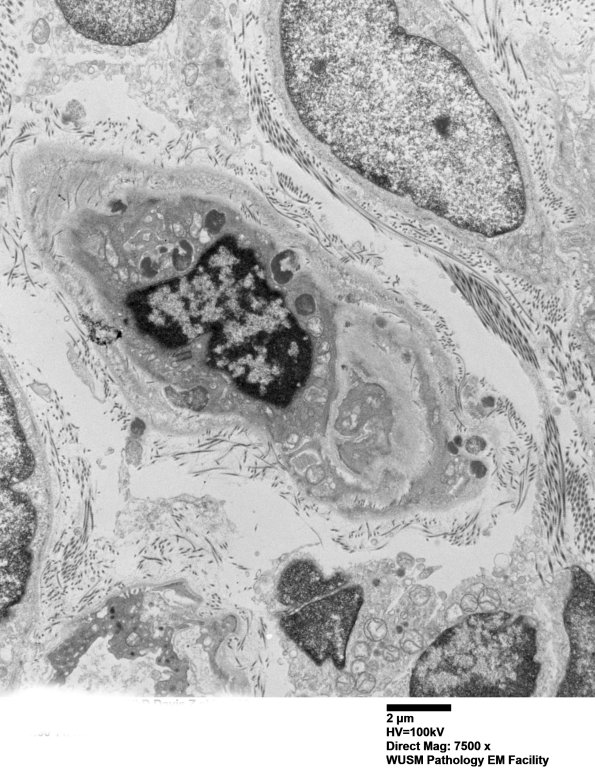

11C2A A low magnification image of a small vessel with a thin smooth muscle partial layer. (electron micrograph)